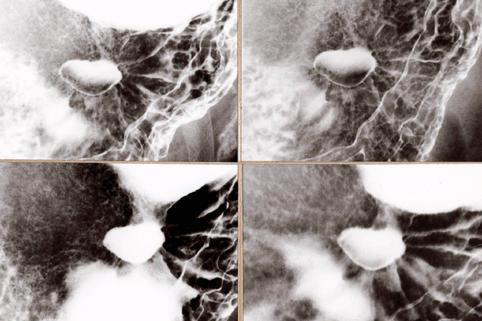

Caso TIC(Conferencia TeleImágen de varios puntos del Tubo Digestivo en conjunto)

2005/11/15 |

14 |

masculino |

45-49

1995-1999's case |